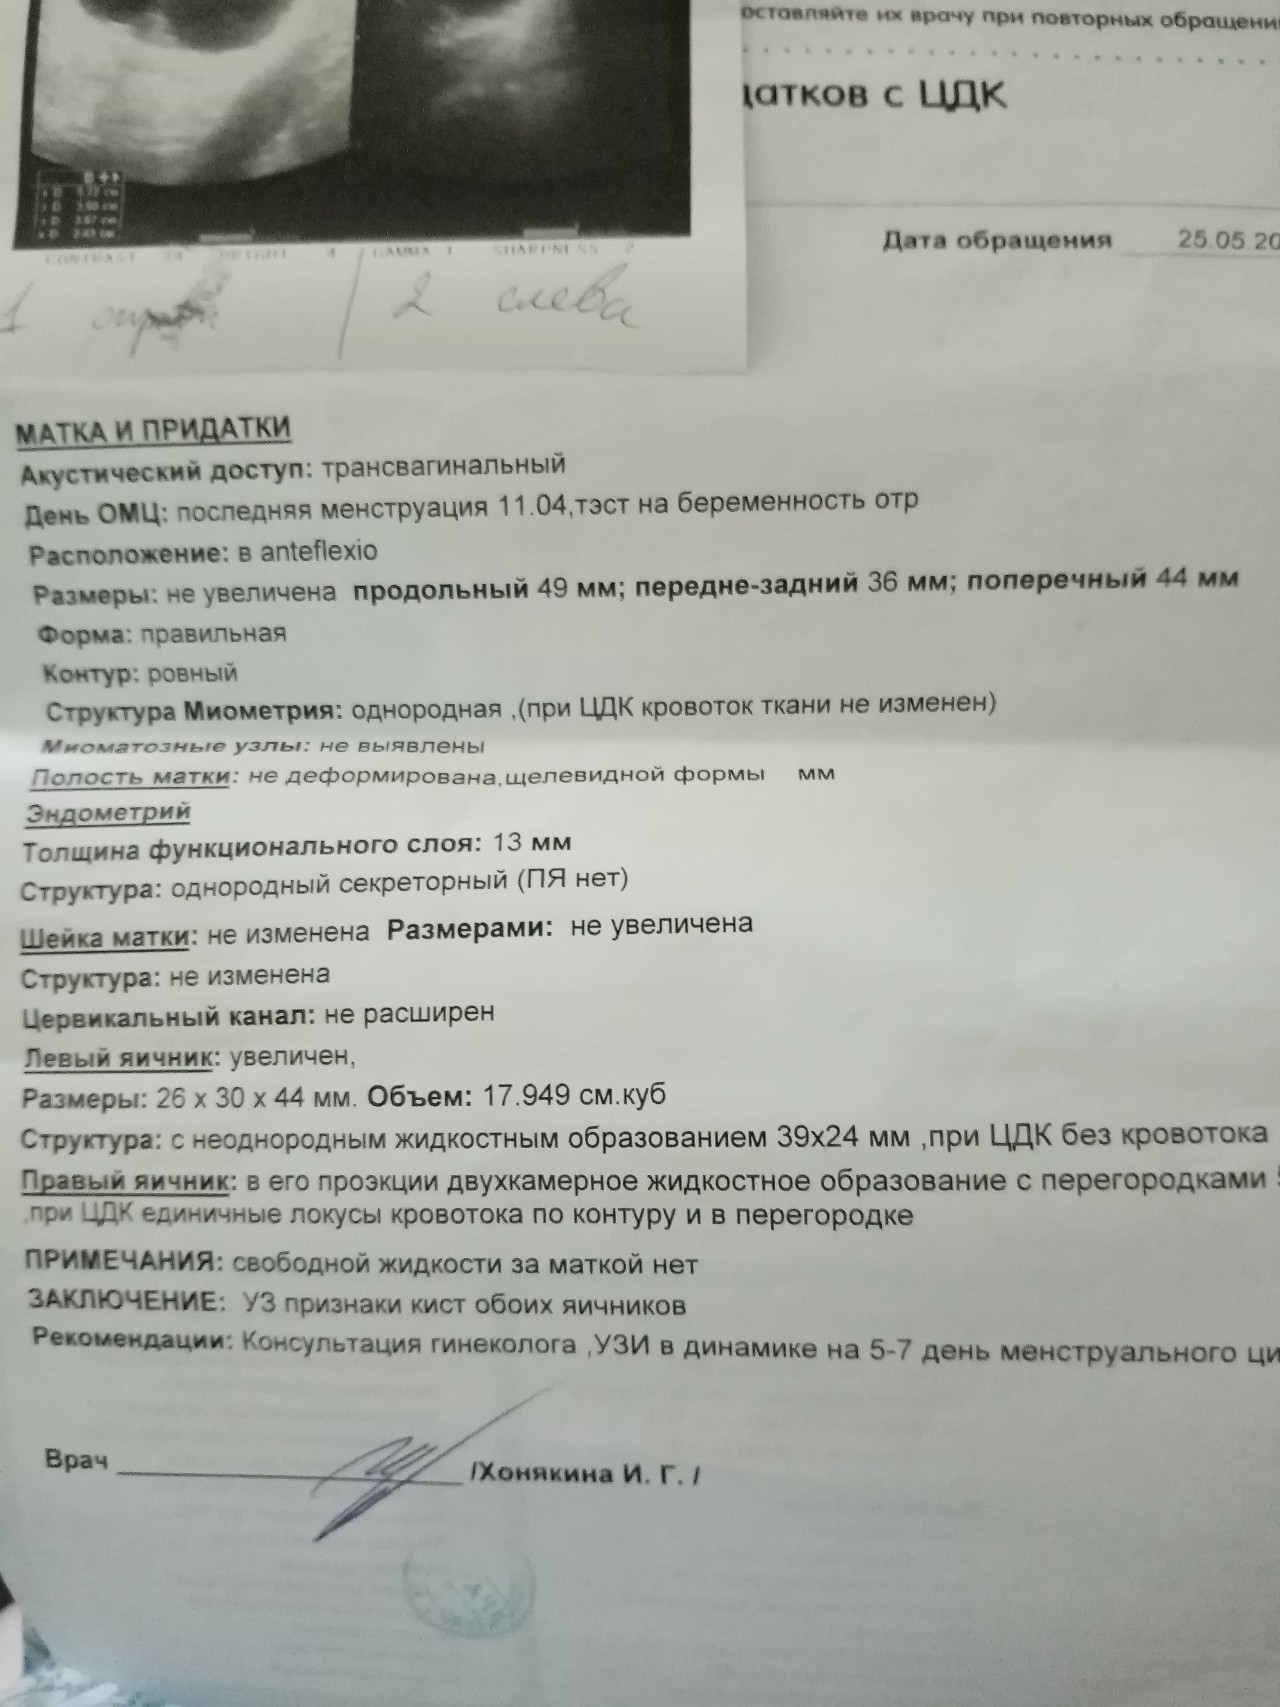

Фотографии на ранних этапах беременности

Раздел: Визуальный дайджест